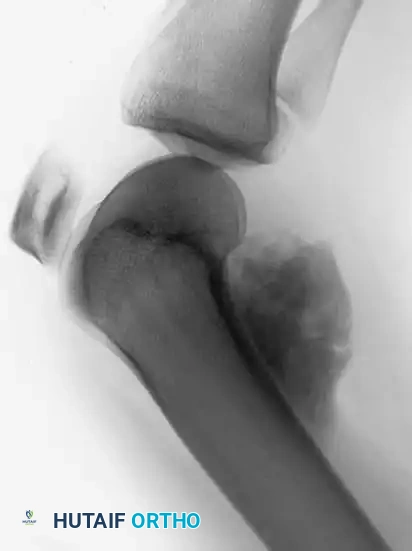

Image

Anteroposterior and lateral radiographs demonstrating a highly aggressive, mixed lytic and blastic osteosarcoma in the distal femur of a 31-year-old man, with cortical destruction and soft-tissue extension.